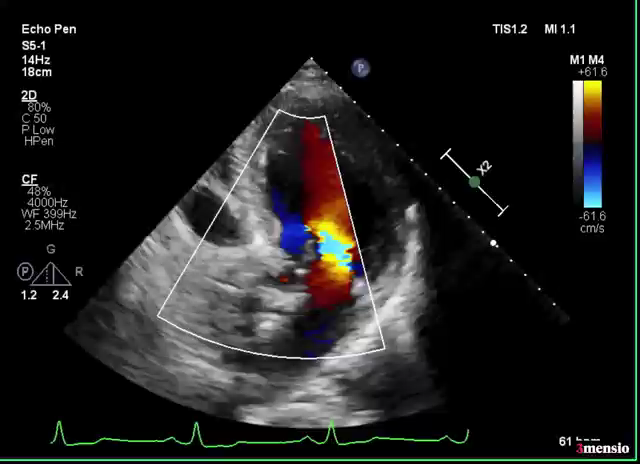

2022年7月6日,葛均波院士及其团队的周达新主任医师、潘文志主任医师、郭克芳副主任医师以及张晓春、张源、陈莎莎、李伟等医师,成功完成世界首例聚合物瓣膜(SIKELIA™)经导管主动脉瓣置换术。该例为80岁男性患者,主要症状为反复活动后胸闷气促,诊断重度主动脉瓣狭窄、心房颤动、高血压。TAVR术程顺利,导管操作时间(skin to skin)27分钟,器械操作顺畅。术后造影显示,瓣膜工作状态良好,跨瓣压差正常,瓣周漏微量。冠脉无阻塞,无传导阻滞。术后即刻拔除气管插管,顺利苏醒。术后六天复查心超提示人工瓣架固定,开放不受限,峰值压差8mmHg,平均压差4mmHg,轻微主动脉瓣反流。患者恢复良好,氨基末端利钠肽前体由术前5688pg/ml下降至1035pg/ml,NYHA 心功能分级由III级改善至II级。术后30天、3个月、8个月随访发现主动脉瓣无明显跨瓣压差,仅微量反流。

术后造影检查

术后随访

8个月随访情况